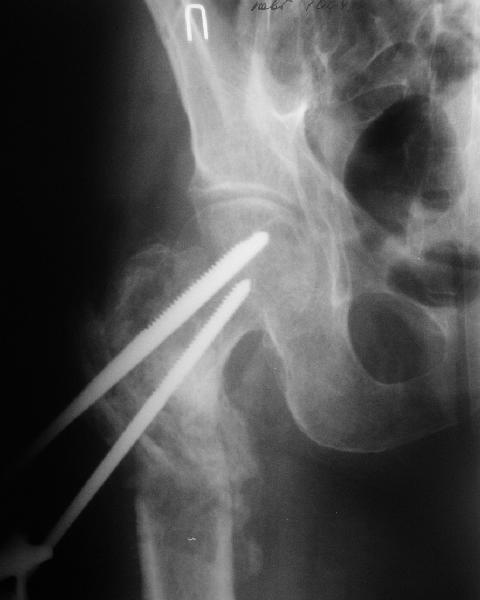

По опыту подобных случаев, аппарат лучше на бедро, без таза пока. В проксимальный фрагмент 3 стержня по оси шейки. Дистальный - хватит 1 стержня или 2 спиц в дистальном метафизе и 1 стержня вверху. Если планируете гвоздь, надо с гиперкоррекцией восстановить длину и ось, т.е. вальгизировать проксимальный отдел. При наложении аппарата сделать остеоклазию, добиться уверенной подвижности. Регенерат не нужен, тяните на пределе переносимости пациентом - хоть 2 см/сут. Обычно меньше.

Второй этап - на следующий день после окончания коррекции.

Если все получилось, т.е. закрыто сопоставить с гиперкоррекцией, накладываете дистрактор таз-бедро или используете тракционный стол, и гвоздь можно делать закрыто. Пластика то есть не нужна. Если клинковая пластина - может получиться как при меежвертельной остеотомии, боковая компрессия by mismatch. Тогда тоже пластика не нужна. Если не получатся, можно и сделать.

В приложении пример пациента, близкого по картине к тому, что представил Виктор (варус и смещение периферического отломка на поперечник кзади). Сделали как раз то, что Виктор исходно намеревался - аппаратная коррекция и затем гамма.